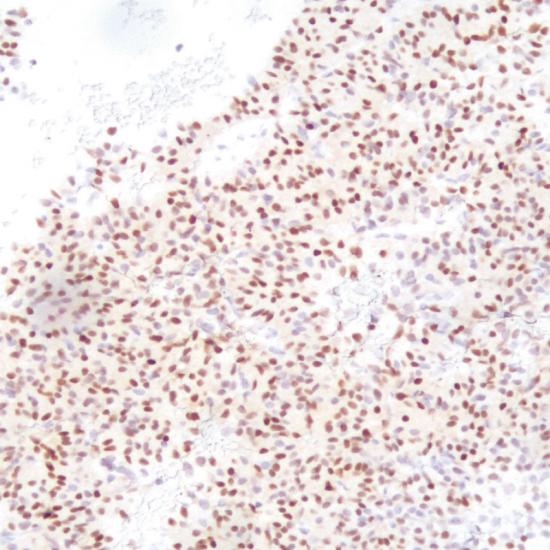

T-PIT(TBX19)

T-PIT抗體試劑(免疫組織化學(xué)法) 閩廈械備20190135號

細胞核

垂體腺瘤

T-PIT(TBX19)是阿片-促黑素細胞皮質(zhì)激素(POMC)譜系與促腎上腺皮質(zhì)激素細胞轉(zhuǎn)錄因子。形態(tài)學(xué)特征和免疫學(xué)標記,用于腺瘤分類的轉(zhuǎn)錄因子可分為三組:嗜酸性譜系,對PIT-1陽性,會導(dǎo)致生長激索瘤,泌乳索細胞和促甲狀腺激索腫瘤;類固醇生長因子-1 (SF-1)陽性的腺瘤,導(dǎo)致促性腺瘤;腺瘤呈T-PIT陽性,導(dǎo)致促腎上腺皮質(zhì)激索腺瘤。